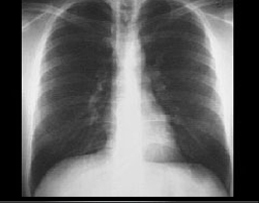

PA and Lateral

Click on the Xrays to enlarge them.

Choose the best interpretation of the chest X rays:

Straight back

Entirely normal

Rib notching

Right-sided aortic arch

Dextrocardia